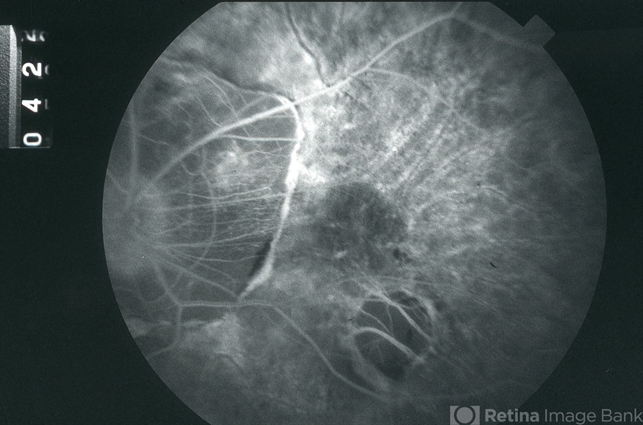

- pathologic myopia, high myopia, fluorescein angiogram (FA), FA mid phase

- Mid-phase fluorescein angiogram image of the left eye of a 51-year-old white male with -25D myopia; V.A. = 20/40